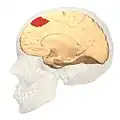

Image of brain with Brodmann area 8 shown in orange | |